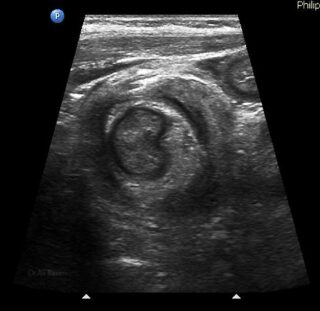

La invaginación intestinal es la causa más común de obstrucción intestinal en niños de 3 meses a 3 años. Se caracteriza porque un segmento de intestino penetra en otro segmento intestinal. Puede presentarse en colon, intestino delgado o entre intestino delgado y el colon. El resultado es la obstrucción intestinal.